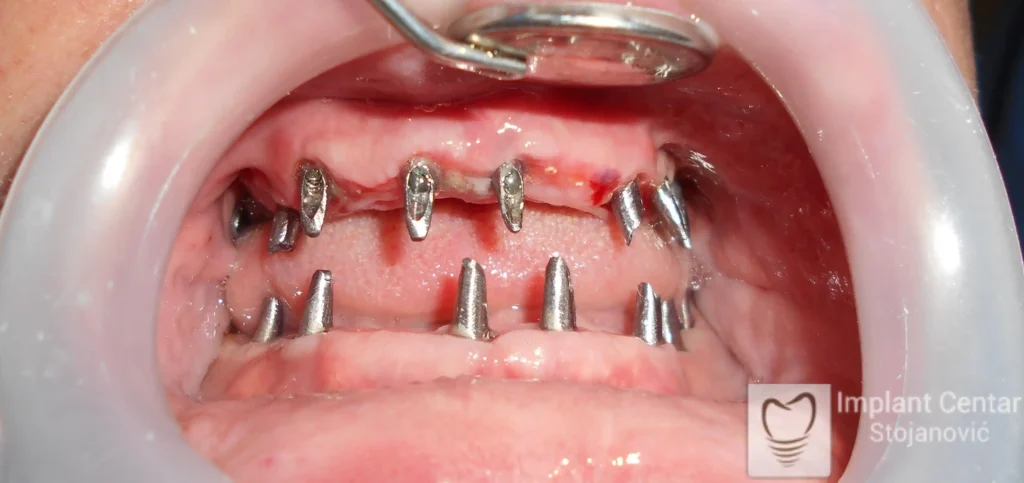

Na slikama 1, 2, 3 , 4  i  5 prikazan je izgled pacijenta pre početka terapije. Nakon detaljne kliničke i radiološke analize, doneta je odluka o vađenju zuba loše biološke vrednosti, dok su bezuba polja sanirana ugradnjom dentalnih implantata.

Nakon ugradnje implantata i pripreme preostalih zuba, pacijentu su izrađene fiksne privremene krunice, čime je postignut eugnatan zagriz već nakon jednog dana (slika 8, 9 i 10). Tokom perioda osteointegracije, pacijent se postepeno privikavao na novi položaj vilica i zagriz.

Po završetku perioda integracije, izrađeni su definitivni cirkonijum-keramički mostovi, čime je postignuta potpuna rekonstrukcija zagriza, kao i značajno poboljšanje estetike i oralne funkcije (slika 12, 13, 14 i 15).

Pacijent je izrazito zadovoljan postignutim rezultatom, kako funkcionalno, tako i estetski, uz značajno poboljšanje kvaliteta svakodnevnog života.